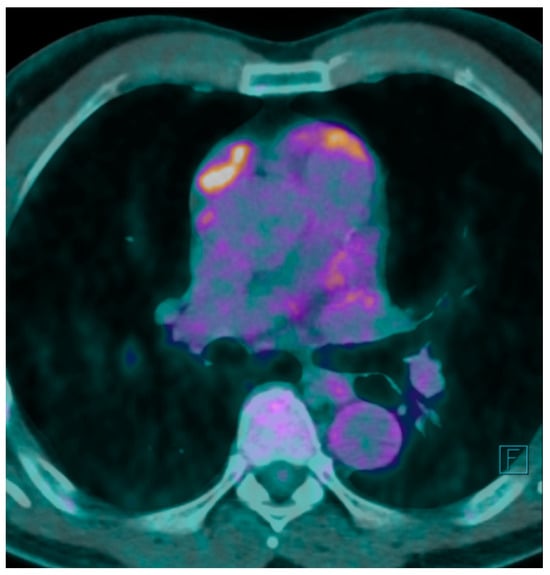

A F18 fluorodeoxyglucose-positron emission tomography (F18 FDG-PET) scan was performed showing a maximum F18 FDG Standard Uptake Value (SUV) of 7.7 at the level of the mass. The FDG uptake appeared to be heterogeneous for the presence of photopenic areas mainly due to the cystic aspect of the mass (Figure 1).

Figure 1. PET-CT shows uptake of F18 FDG in correspondence with anterior mediastinal mass. Brighter colors such as white, yellow and orange denote a higher F18 FDG uptake.